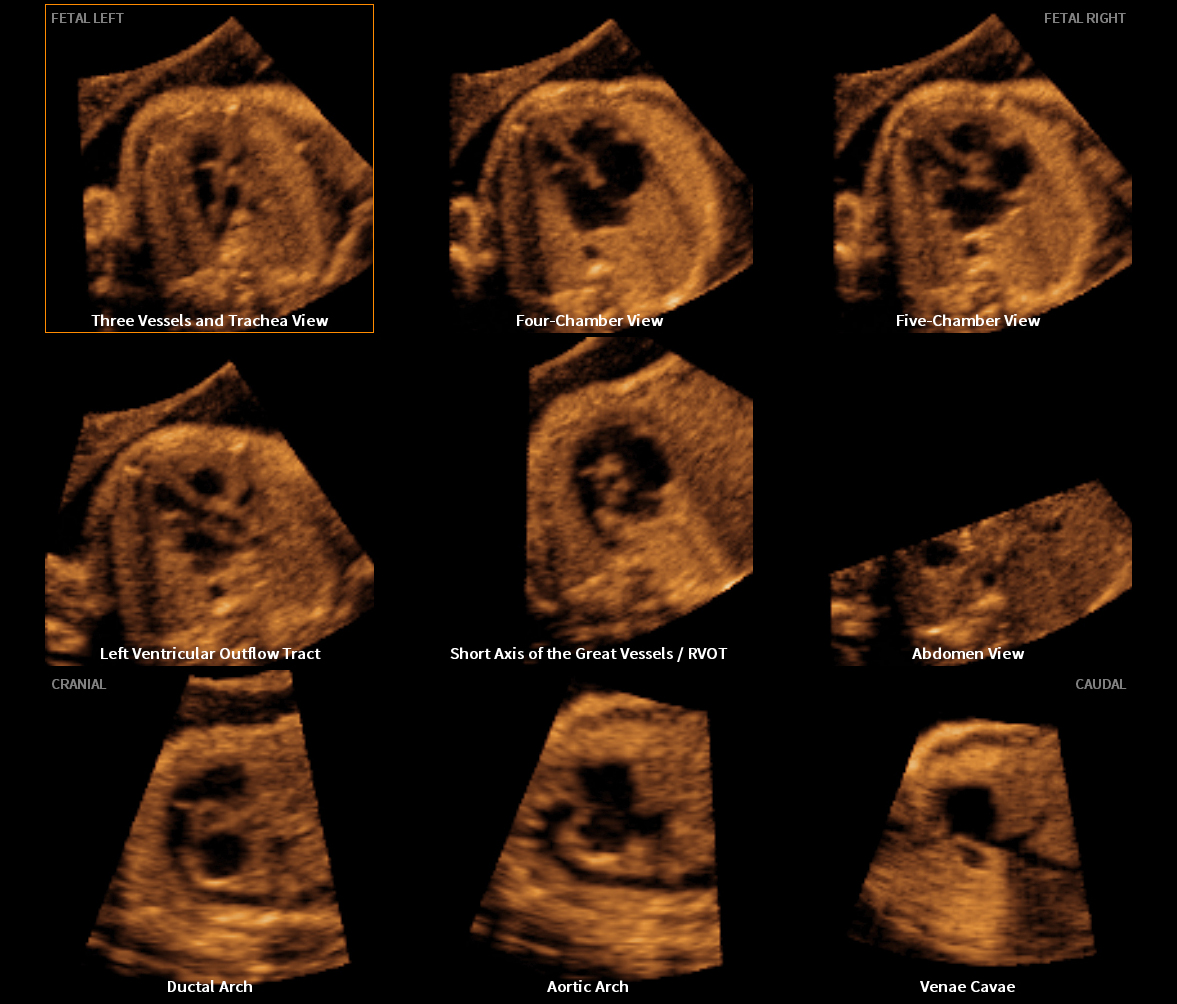

Samsung Presents Clinical Usability of its Ultrasound Imaging Technology at ISUOG 2017

Samsung Medison, a global medical equipment company and an affiliate of Samsung Electronics, is hosting a number of seminars at the 27th World Congress of the International Society of Ultrasound in Obstetrics & Gynecology (ISUOG) in Vienna. Through 13 sessions at Samsung’s Satellite Symposium, leading medical professionals are publicizing the clinical benefits of Samsung’s ultrasound imaging solutions for women’s health.